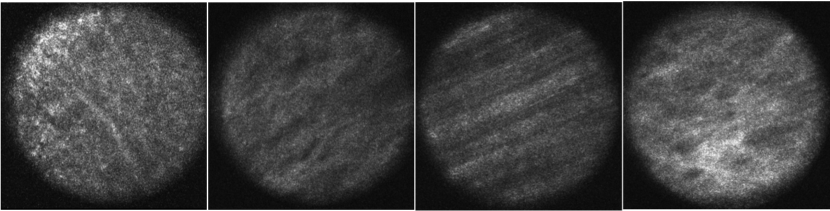

?figurename? 1: Examples of the four different classes. From left to right, healthy colon tissue, malignant colon tissue, healthy peritoneum tissue and malignant peritoneum tissue.

The dataset we use was kindly provided to us by the authors of a previous study on CLM [3]. The dataset was acquired at the University Hospital Schleswig-Holstein in Lübeck using a custom intraoperative CLM device. The CLM device (Karl Storz GmbH & Co KG, Tuttlingen, Germany) covers a field of view of 300 µm×300 µmtimes300micrometertimes300micrometer$300\text{\,}\mathrm{\SIUnitSymbolMicro m}$\times$300\text{\,}\mathrm{\SIUnitSymbolMicro m}$ with a resolution of 384×384384384384\times 384 pixels. The images were obtained from ten rats where colon adenocarcinoma cells had been implanted into the colon and peritoneum seven days before scanning. For each subject, images of healthy colon tissue (HC), malignant colon tissue (MC), healthy peritoneum tissue (HP) and malignant peritoneum tissue (MP) were obtained. In total, there are 533 images of class HC, 309 images of class MC, 343 images of class HP and 392 images of class MP which results in a total dataset size of 1577 images. Note, that for one subject there are no images of class HC and for one subject there are no images of class MP. Example cases for each class are shown in Figure 1. The assignment of classes for each image was performed based on subsequent histological evaluation of resected tissue from the scanning area.